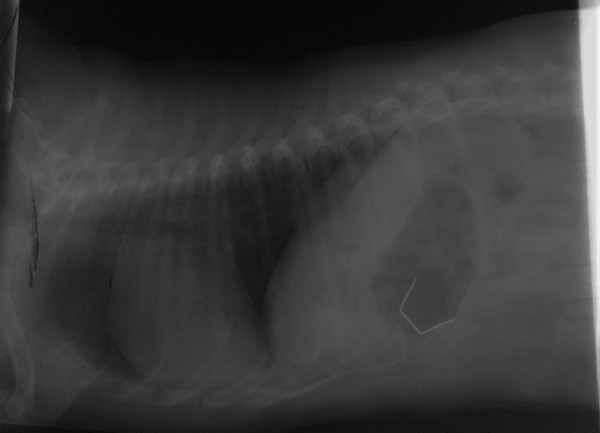

I have to confess, that it took us a few xray views and a thorough investigation of our xray plates, xray table and xray developing machine to convince ourselves and the owner that the object showing on the xray was really inside Hara's stomach and it was not an xray artifact!!!

Having confirmed the presence of this weird foreign body inside the little dog's stomach.............without any help from "her", as she was denying with passion her guiltiness, continuously showing off her beauty and her braid, looking innocent and cute........we were left with no other choice but to "grill" the owner!

The obvious thing was that the foreign body was a staple! Its size though, was not of an ordinary office staple. We were running out of ideas as to where she could have possibly found it and we had accused friends and relatives for not cleaning their floors................when the owner confessed that Hara is quite "naughty" at home ...........but she gets away with almost everything as soon as she waves that .......braid!

To be perfectly honest though, we ended up riping apart one of the clinic's sofas to get one of these staples and xray it by the side of Hara's belly, only to confirm that the one inside her stomach was of the same shape and size as the staple that holds the covers of the sofa together!!!